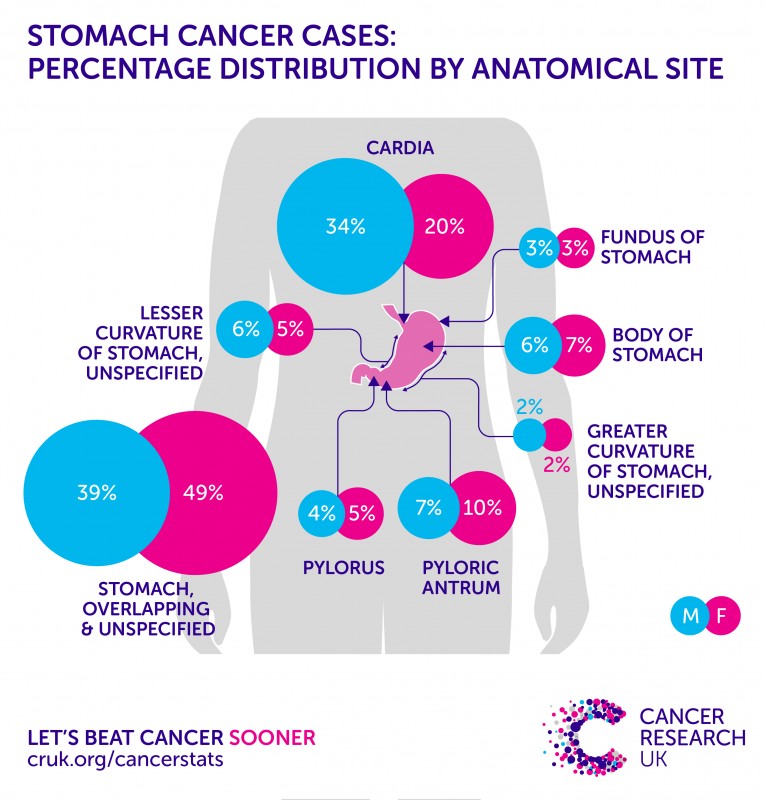

Stomach Cancer | Symptoms, Causes, Stages, Treatment and Survival Rates

Stomach Cancer | Symptoms, Causes, Stages, Treatment and Survival Rates

Genomics and Targeted Therapies in Gastroesophageal Adenocarcinoma …